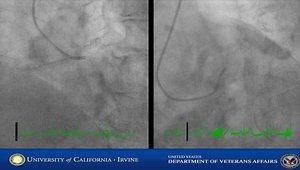

Fractional Flow Reserve Procedure

Fractional Flow Reserve (FFR)

Fractional Flow Reserve Coronary CTA

FFR Basics, Practice, Pitfalls - Mort Kern